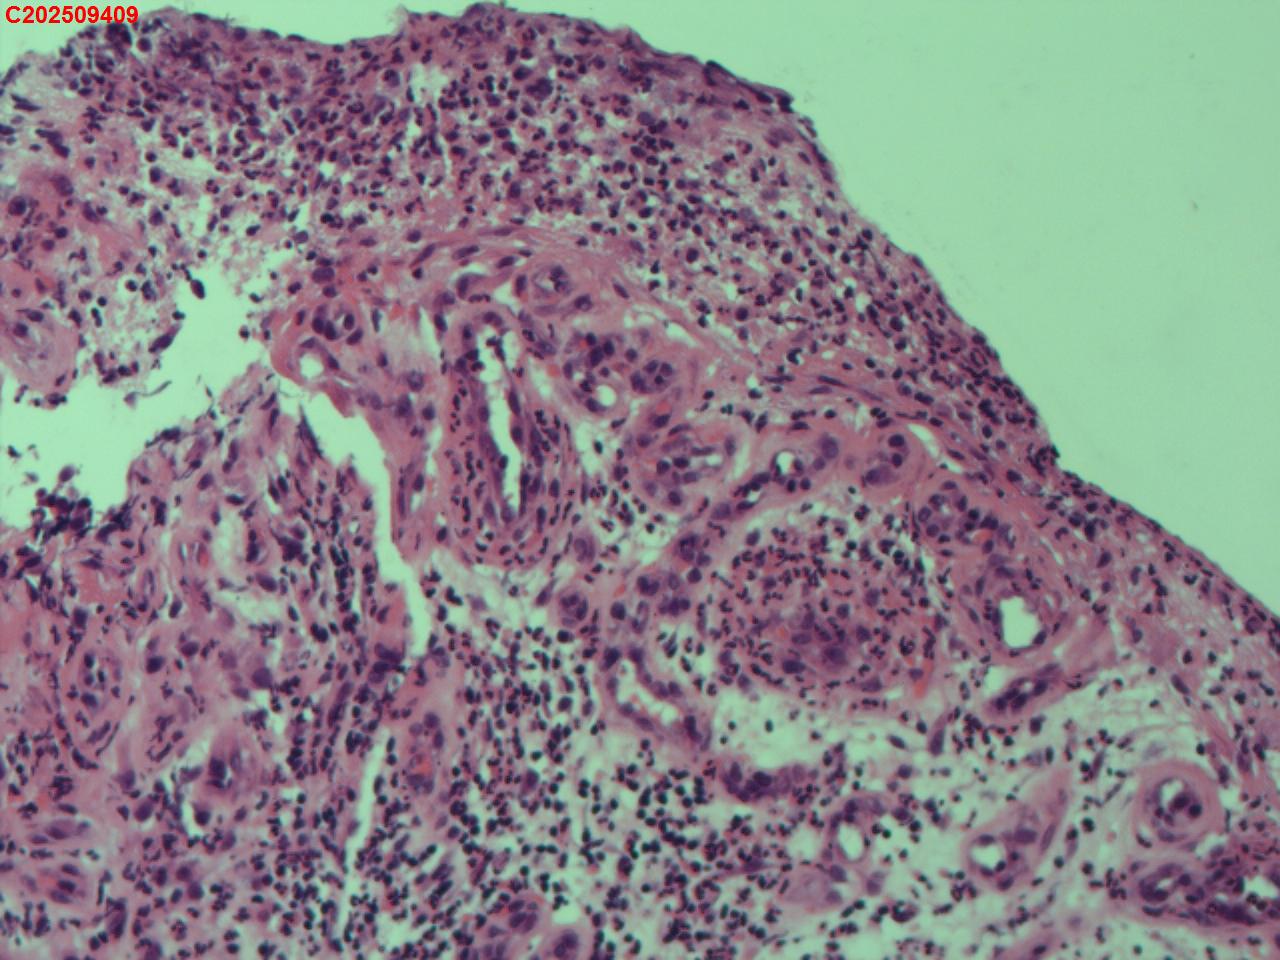

性别年龄62岁临床诊断社区获得性肺炎,肺占位性病变带除外

一般病史胸部CT:双肺可见多发斑片状、结节状高密度影,右肺上叶及左肺下叶病灶内见多发空洞,右侧少量胸腔积液。

标本名称纤支镜咬检

大体所见纤支镜:气管通畅,隆突锐利。右肺主支气管通畅,右肺上叶见少量痰液,负压吸引后见上叶开口干酪坏死物质附着,上叶各段级支气管通畅未见新生物及坏死物质,中叶、下叶背段支气管通畅,下叶基底段见新生物阻塞气道,粘膜无充血。左肺主支气管、上叶、下叶及各段级支气管通畅,粘膜无充血,未见新生物及坏死物。

考虑:支气管炎性息肉